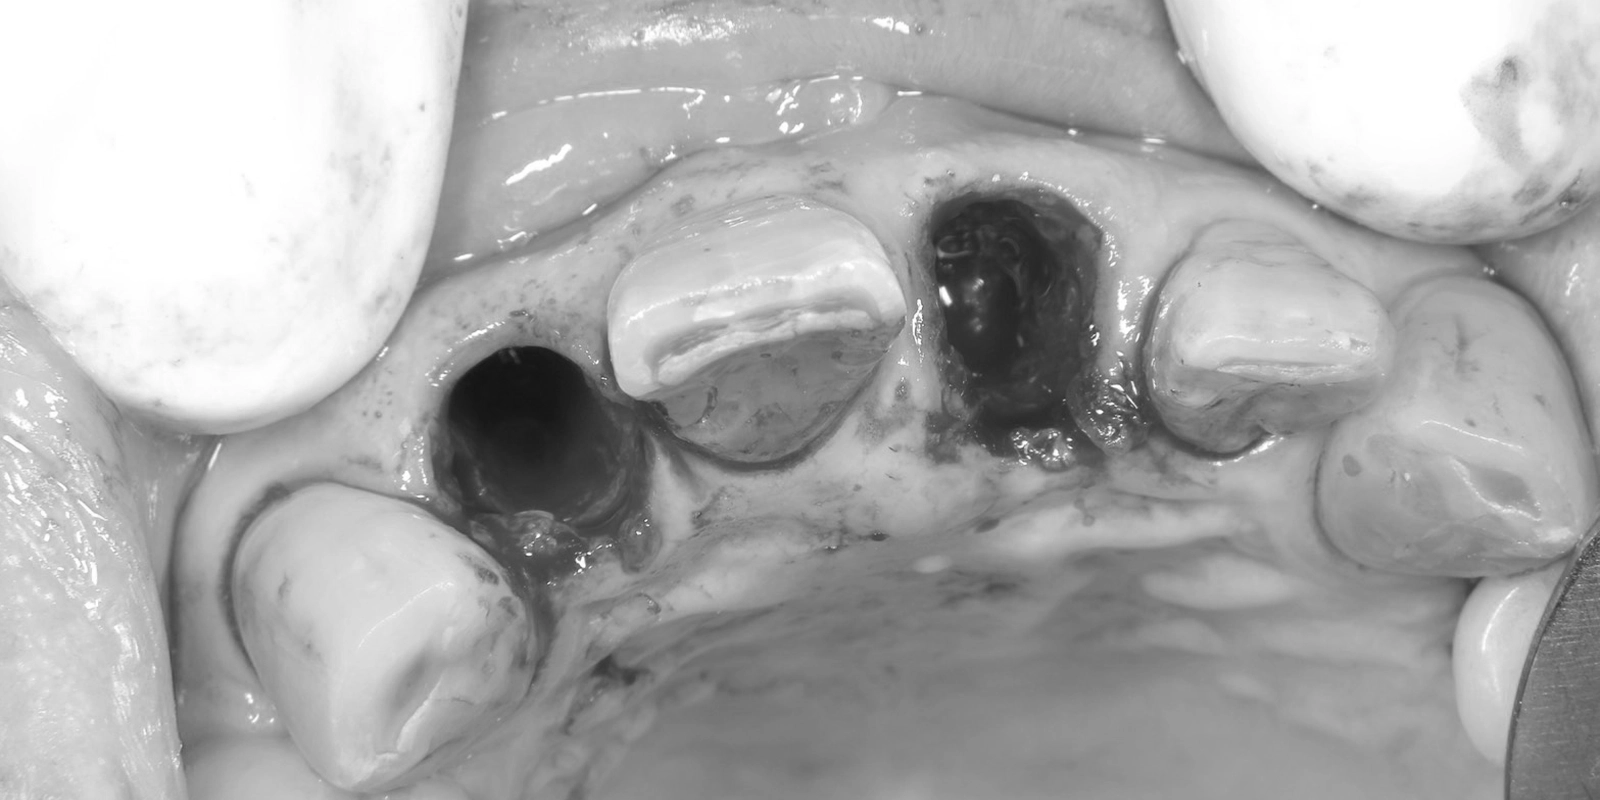

レントゲン写真では、当院で治療した「2本のインプラント体」が骨の中にしっかりと埋入されていることが確認できます。(*治療前のレントゲン写真を見るとわかる通り、当院で治療する前から1本インプラントが入っていたので、治療後は合計3本のインプラントが埋め込まれていることになります。)

そして、インプラント(写真内に写っている白いネジ状の物体)の周囲に骨が十分に存在しており、骨吸収(骨が溶けて減ること)は認められません。

抜歯と同時に埋入を行ったにもかかわらず、周囲の骨がしっかりと保たれていることは、抜歯即時埋入の大きな利点です。